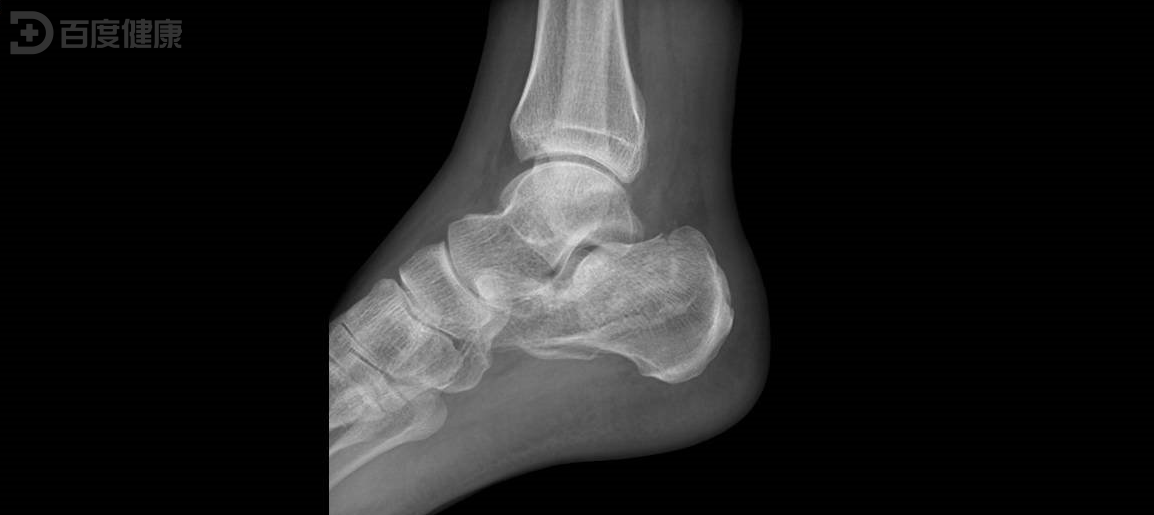

证券之星消息,根据天眼查APP数据显示威高骨科(688161)新获得一项发明专利授权,专利名为“一种用于跟骨置换的定制跟骨假体及制造方法”,专利申请号为CN202210946586.5,授权日为2025年7月18日。

专利摘要:本发明属于骨科医疗器械领域,提供一种用于跟骨置换的定制跟骨假体及制造方法,跟骨假体的结构特征基于患者足部骨骼形态设计,包括跟骨假体主体,所述跟骨假体主体上设有跟距关节面、跟骰关节面、跟腱孔、锁定螺钉孔、足跟支撑面、跟腱拉环、距骨填充结构、骨小梁多孔结构;由于跟骨假体采用了功能集成的一体化设计,本发明采用3D打印技术与常规机加工相结合的方式进行加工,减低加工难度,提高加工效率,实现锁定螺钉打入骨骼准确的位置和方向,及锁定螺钉与锁定螺钉孔之间螺纹的高精度啮合,锁紧稳固。